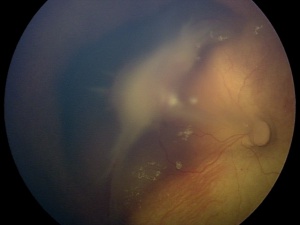

The characteristic findings in the posterior PFV syndrome include leukocoria, microphthalmia, a retinal fold possibly causing tractional retinal detachment of the posterior pole, a hypoplastic or dysplastic optic nerve, vitreous membranes and stalk, macular pigmentary disruption or hypoplastic macula, a clear lens, and strabismus. While 62% of the time PFV may present as a combination of the anterior and posterior syndromes, prognostically it is beneficial to categorize individuals into an anterior, posterior or combination of the syndromes due to patients with the purely anterior form having the most reasonable chance for a successful visual outcome following treatment of their PFV. [20] Although a posterior PFV syndrome does suggest a poorer visual outcome, other factors individually such as the severity of the anterior segment, the size of the globe, the gravity of lens involvement or even the vascular appearance does not seem to predict the amount of retinal dysplasia, which ultimately tends to determine the eye’s visual result. [11]

PFV is most readily diagnosed by direct visualization of any component of the persistent fetal vasculature with a careful examination. In patients with poor view of the fundus, ultrasonography can be employed. In general, ultrasound, computed tomography scanning, magnetic resonance imaging, and fluorescence angiography are all reasonable options for establishing a diagnosis. The most important differentiation when obtaining imaging is differentiating PFV from the malignant retinoblastoma (Rb). B-scan ultrasonography and computed tomographic scanning can be exceptionally helpful in this regard. Calcification seen on imaging is suggestive of malignancy due to calcification rarely being seen in PFV alone. A foci of calcification is present in 90% of retinoblastoma cases, making calcification highly suggestive of malignancy, especially if visualized in a child less than three years old. [21] B-scan ultrasonography can be used to assess for intraocular masses, fibrovascular stalk, microphthalmia and to look for calcification. In addition, Doppler associated ultrasonography can be quite useful to detect vasculature associated with PFV. [22]

Likewise, if an MRI were to be used, the MRI findings would include: a tubular structure, representing the hyaloid vessel; a funnel-shaped retinal detachment, with the subretinal fluid hyperintense on both T1 and T2 weighted images; fluid-fluid level due to the presence of hemorrhage in the subretinal space, a retrolental mass; micro-ophthalmia, and vitreous hemorrhage.” [16]